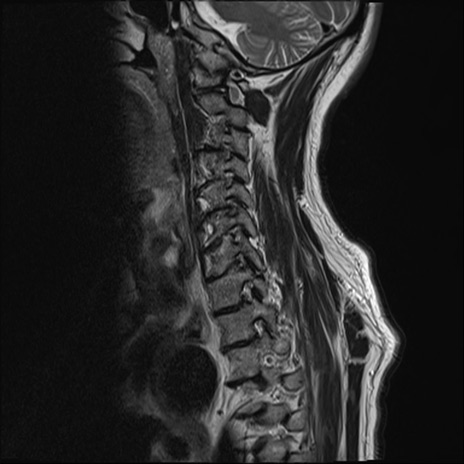

【整形】TIPS症例7 頚椎MRI T2WI(矢状断像)

頚椎MRI

矢状断像と横断像